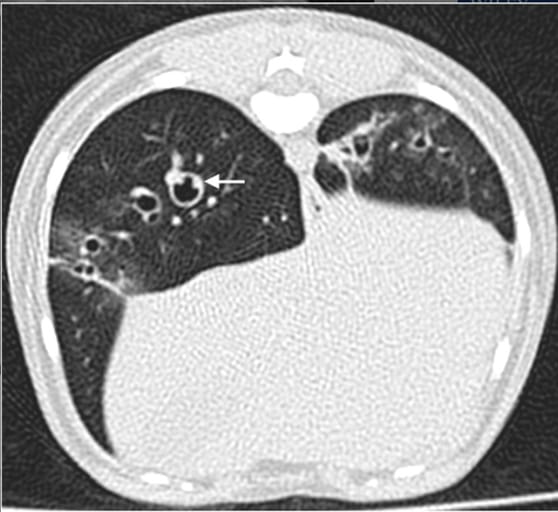

Noncontrast transverse CT image of dog 3 in a lung window. Note the bronchial wall thickening and two bronchial mural nodules (arrow) protruding within the lumen of one segmental bronchus of the right caudal lung lobe. Severe parenchymal bands and mild ground glass lesions are also identified in both hemithoraces. WW = 1400, WL = −500

All three dogs exhibited multifocal, peribronchial pulmonary lesions. CT abnormalities included diffuse bronchial wall thickening (moderate to severe), multifocal peribronchial ground-glass attenuation, alveolar infiltrates, cylindrical bronchiectasis, and parenchymal bands. In one dog, bronchial thickening appeared nodular, consistent with bronchoscopic findings of irregular mucosa. No lymphadenomegaly, pleural effusion, or pulmonary hypertension was detected. All dogs clinically recovered following antiparasitic treatment.